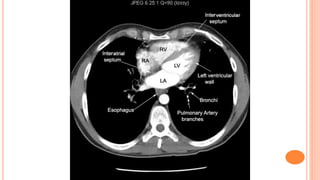

(2) CT

CT at level of Carina

CT at levelof Carina